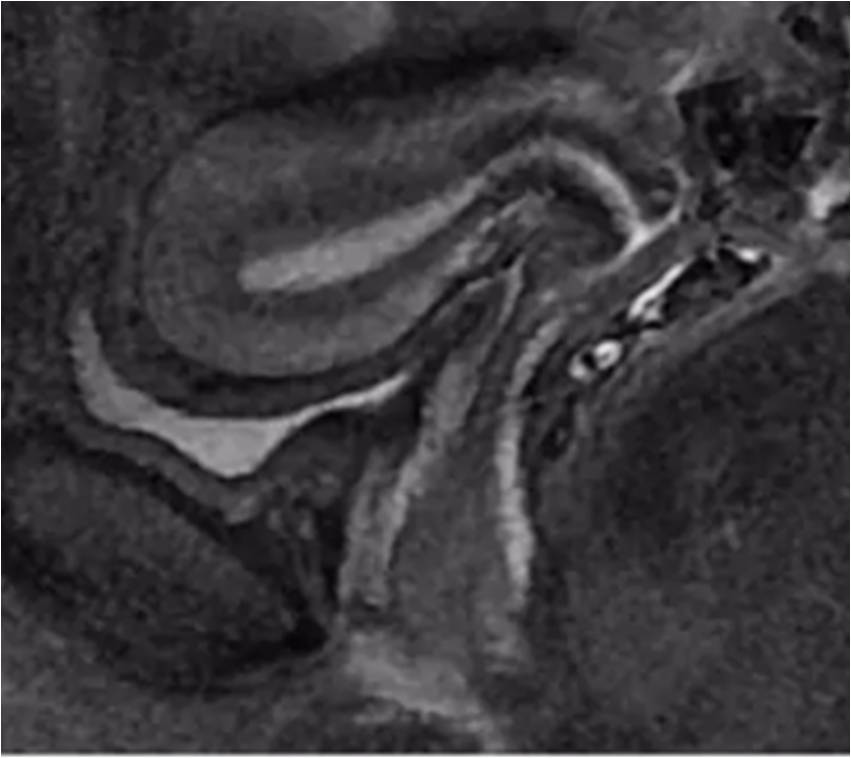

2. 子宮頸(T2WI):

最內層-高信號粘液

粘膜層(柱狀上皮)-高信號,低于粘液信號

纖維基質(結合帶)-低信號

肌層-中等信號